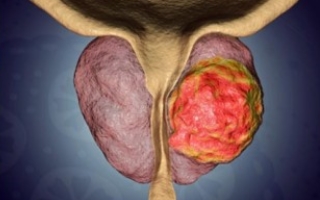

많은 남성들이 나이가 들면서 빈뇨, 실금 또는 약한 오줌 줄기 등 배뇨에 문제가 생긴다. 보통 이는 전립선이 커진 징조이지만 전립선암을 의미할 수도 있다. 검사 또는 특수 혈액 검사 PSA검사를 위해 병원에 가보는 것이 좋다. 부어오른 림프절로, 목 ,겨드랑이, 그리고 다른 신체 부위에 콩 모양의 작은 분비선이 부을 경우, 이는 감기나 인후염 같은 감염과 싸우고 있다는 뜻이다. 림프종이나 백혈병과 같은 몇몇 암 역시 이런 종류의 붓기를 일으킬 수 있다.

변기에 피가 있는 것을 본다면 의사와 즉시 상담하는 것이 좋다. 혈변은 치질로 인한 부풀어오르고 염증이 있는 정맥에서 나올 가능성이 높지만 대장암일 가능성도 있다. 혈뇨는 요로감염과 같은 문제가 될 수 있지만 신장암이나 방광암일 수도 있다. 고환에 혹이 생기거나 붓는 것을 발견하면 의사의 진찰을 받아야 한다. 통증이 없는 혹이 생기는 것은 고환암의 가장 흔한 징후이다. 아랫배나 음낭에 무거운 느낌이 들거나 고환이 더 크게 느껴질 수 있다. 초음파 검사를 하자.